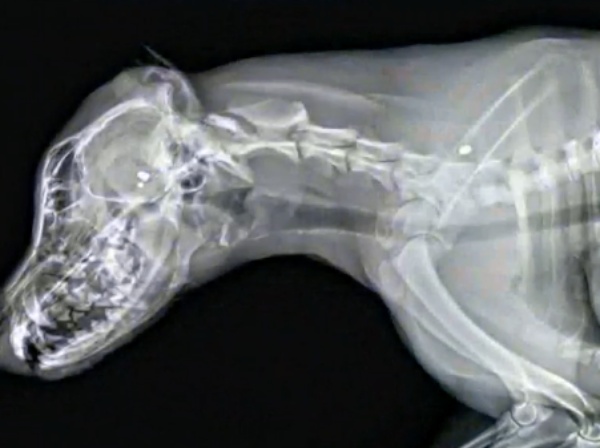

Since the family was not home and did not have any surveillance camera, they have no idea when the dog first showed signs of injury or how long she suffered. While at the emergency hospital, the veterinarian on call revealed Dixie had been shot three times with a pellet gun. The rounds are called “diablo” pellets, and the sheriff says they are common in airsoft guns. Dixie was in a fully fenced-in yard when she was shot, and there was no evidence of a break-in.